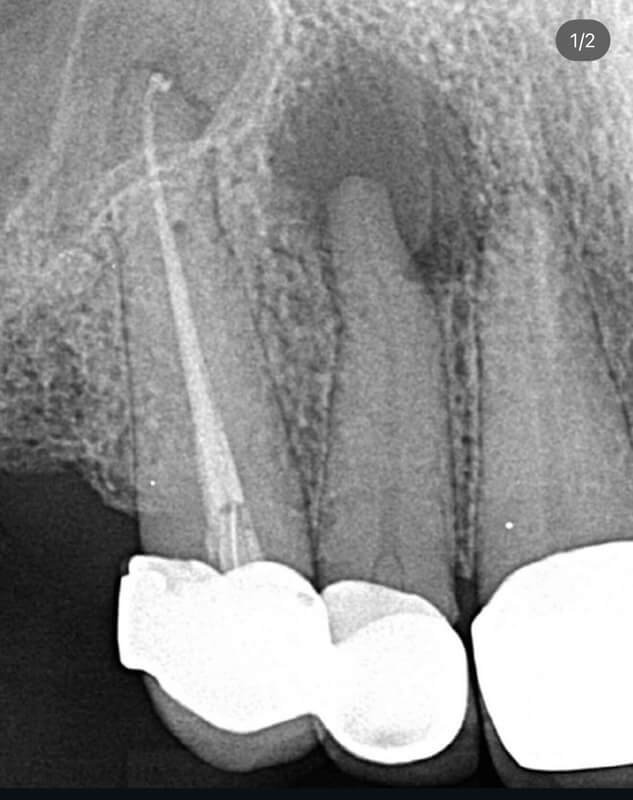

Endodonția este o ramură esențială a stomatologiei, axată pe diagnosticarea, prevenirea și tratamentul afecțiunilor pulpei dentare și a țesuturilor periapicale. Această specialitate joacă un rol crucial în salvarea dinților naturali, evitând extracțiile și menținând sănătatea orală pe termen lung. Prin tehnici avansate și echipamente de ultimă generație, endodonția asigură tratamente precise și eficiente, contribuind la redarea sănătății și funcționalității dinților într-un mod durabil și predictibil.

Utilizarea tehnicilor moderne asigură un tratament rapid, precis și confortabil pentru pacient.